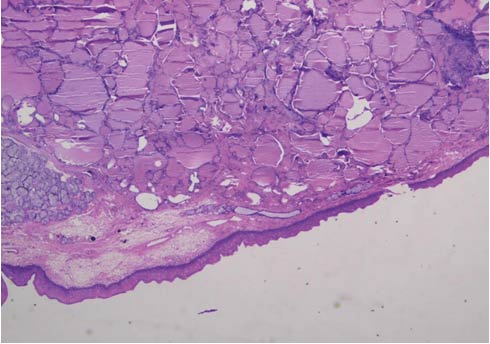

Microscopic description of the resected mass: Sections show stratified squamous epithelial lining. The subepithelial stroma shows islands of normal thyroid follicles and a few seromucinous salivary glands, with mild lymphoid cell infiltrate. There was no evidence of malignancy. (Figure 3 and 4)

Figure 4.  Photomicrograph of Histology Section, H & E Stain, 20 X, With Similar Features as in Figure 3.

Conclusion: Excised swelling base of tongue - LINGUAL THYROID.